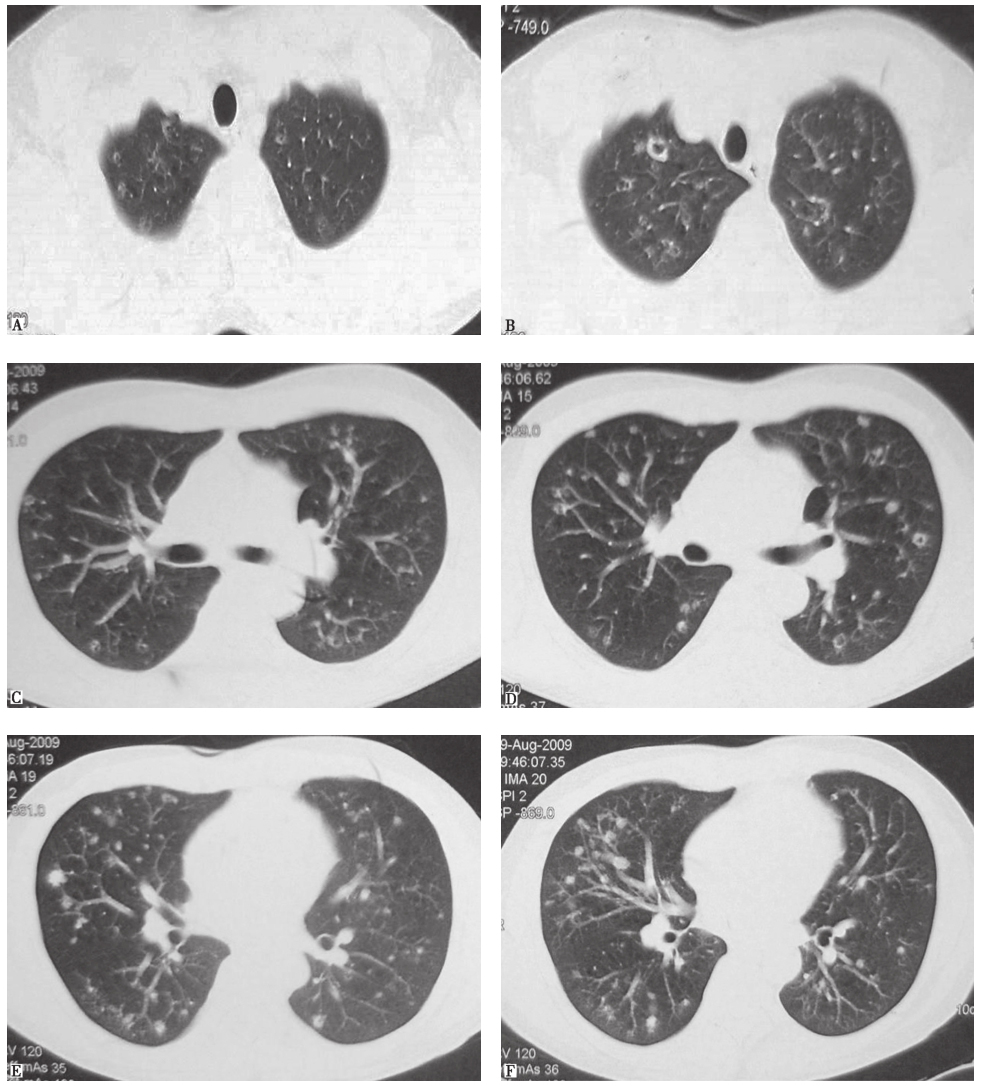

胸部CT可见双肺多发小叶中心型小结节影,部分为空泡影,病灶以中上肺分布为主,肺底病变不明显,散在分布(图1)。

图1入院前3周胸部CT表现

4.胸部CT可见双肺沿支气管走行分布为主的多发结节及空洞,以中上肺分布为主,肺底和膈肋角肺野病灶稀少。

一些非感染性疾病的胸部影像学表现也可见肺内多发结节、空洞影:①恶性肿瘤肺内转移,包括肺外肿瘤或原发肺肿瘤肺内转移,一般病灶的时相一致,转移结节在分布上呈现随机性,无明显中上肺部分布倾向;②职业肺病:多种金属粉尘暴露所致肺病的胸部影像学表现可见肺内随机分布或沿气道分布的结节,但一般没有空洞影。本例患者无类似暴露史,故不考虑职业肺病可能;③肺朗格汉斯细胞组织细胞增生症(pulmonary Langerhans cell histiocytosis,PLCH):以过量活化朗格汉斯细胞(Langerhans cell,LC)在器官内增殖、浸润为特征,病理特征为特异的组织细胞(朗格汉斯细胞)增殖,伴嗜酸细胞浸润。肺内病变可以为边界不清的结节影、空洞影、囊泡影。病变早期以小叶中心性结节为主,直径在1~5mm;病程后期表现为弥漫分布的囊泡影,囊泡壁厚薄及大小不一、形态不规则,囊泡直径通常为1cm,最大可至3cm;胸膜下肺大疱也不少见。病灶以双中上肺分布为著,自上而下发展,双侧肋膈角一般不受累。疾病晚期,病灶可以累及全肺。对于本病例,结合影像学表现,需要高度怀疑PLCH的可能。

PLCH患者HRCT可见特征性表现:病灶多分布于双肺中上,双侧肋膈角一般不受累,以多发边界不清的结节影、空洞影、囊泡影多见;病变早期以小叶中心性结节为主,直径为1~5mm;病程后期表现为弥漫分布的囊泡影,囊泡壁厚薄及大小不一、形态不规则,胸膜下肺大疱也不少见;晚期,病灶可以累及全肺。支气管镜检查(包括支气管肺泡灌洗、经支气管肺活检)有助于该病的诊断和鉴别诊断。